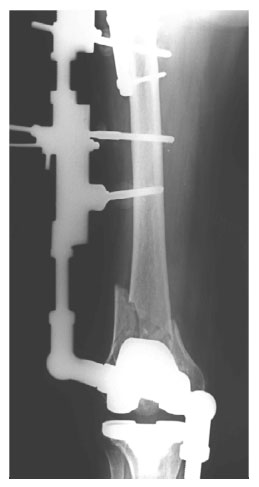

Первичная лечебная чрезсуставная иммобилизация стержневым аппаратом